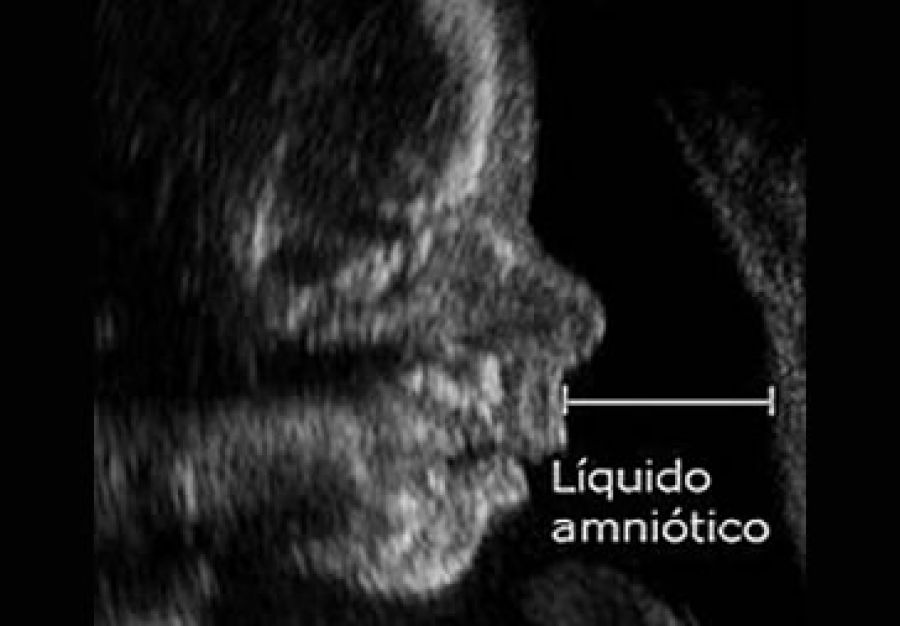

La ruptura prematura de las membranas (RPM) se define como la salida de líquido amniótico a través de una solución de continuidad de las membranas fetales después de las 20 semanas de gestación y al menos una hora antes del inicio del trabajo de parto . Está asociada con infección perinatal, compresión del cordón umbilical y parto pretérmino lo cual es 2 veces más común en la RPM, entre otras complicaciones, las cuales aumentan conforme disminuye la edad gestacional al momento de la ruptura.

Es responsable del 30% de los nacimientos pretérmino en nuestro país siendo una de las causas importantes de morbilidad perinatal y se le ha relacionado hasta con un 10% de la mortalidad perinatal. El diagnóstico oportuno es fundamental para evitar complicaciones del embarazo a causa de la RPM. Ante esta problemática, Gedeon Richter, compañía farmacéutica multinacional especializada en innovación, pone a disposición del mercado mexicano un método de detección de pérdida de líquido amniótico que no es invasivo, y que está novedosamente aplicado en un panti-protector (pad) que se adhiere a la ropa interior y es una prueba sumamente precisa y ambulatoria.